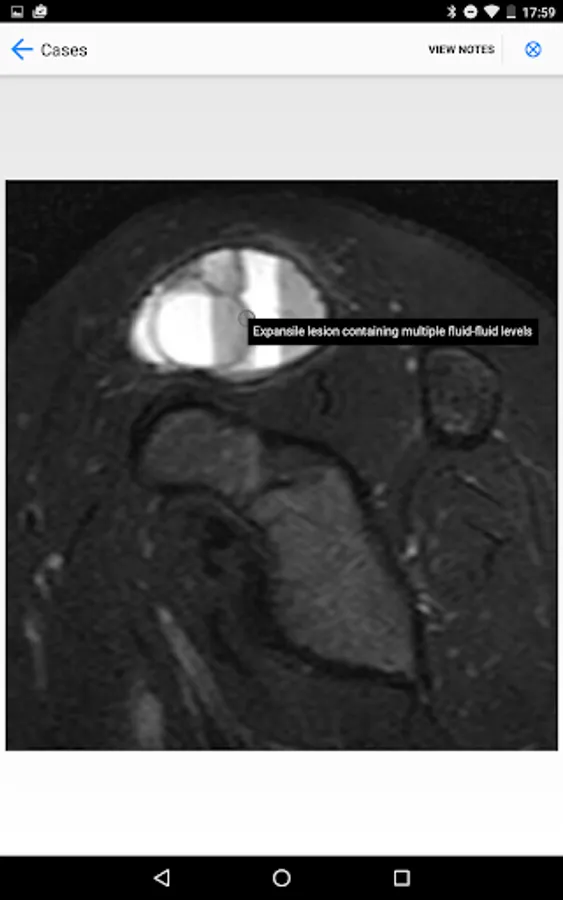

BoSTT brings the user a real experience of frequent and rare, typical and more unusual cases of bone and soft tissue tumours. Each case has a clinical history, high resolution radiology and pathology images, diagnosis, treatment and learning points.